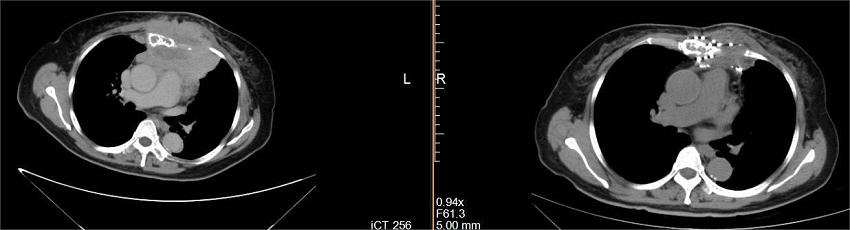

介入穿刺针

碘-125放射性粒子

放射性粒子植入属于组织间植入近距离治疗范畴,是放射治疗的方法之一,主要通过影像引导技术(CT、彩超、磁共振)通过介入穿刺针,像子弹一样将密封的放射源直接打入肿瘤病灶内,通过放射性核素持续释放射线对肿瘤细胞进行杀伤的一种治疗手段。放射性碘-125粒子能以27-35kev能量放射出γ射线,半衰期为60.2d。γ射线有效辐射半径10-15mm内肿瘤细胞的DNA,干扰肿瘤细胞DNA合成,诱导细胞凋亡,杀灭肿瘤细胞,小血管,小神经等,达到缩小肿块,缓解疼痛的目的。放射性粒子在治疗实体肿瘤具有精度高、创伤小和疗效肯定等优势,近年来3D打印模版技术的发展进一步提高了精度、安全性,缩短了手术时间。